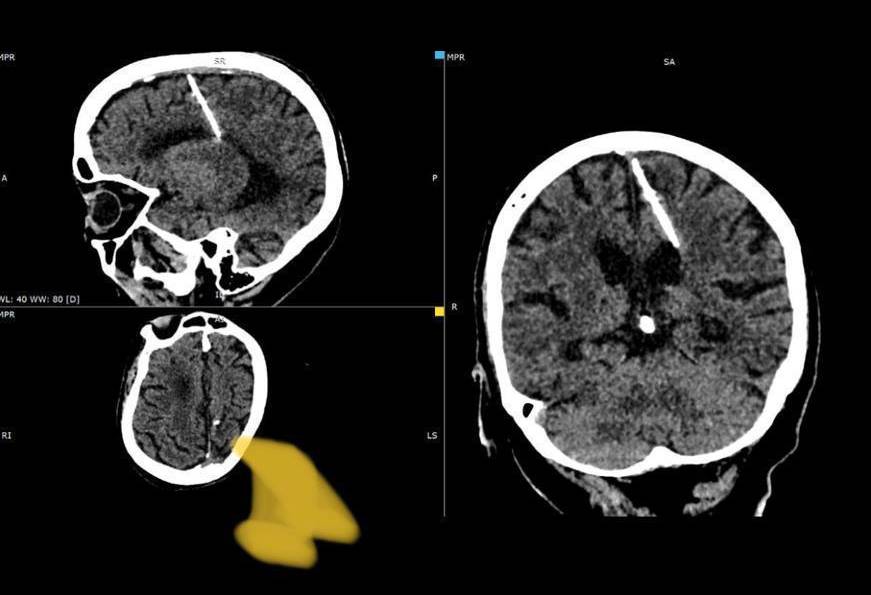

Иглу длиной в 3 сантиметра обнаружили в голове у 80-летней пациентки сахалинские рентгенологи

Игла проникла в левую теменную долю, но это не привело к ожидаемым последствиям – девочка выжила. Более того, в последствии её никогда не мучали головные боли. Инородное тело было выявлено только в этом году при проведении компьютерной томографии.

Здоровью пациентки ничего не угрожает, за её состоянием наблюдает лечащий врач. Оперативное вмешательство было решено не проводить, так как это может только ухудшить её состояние.